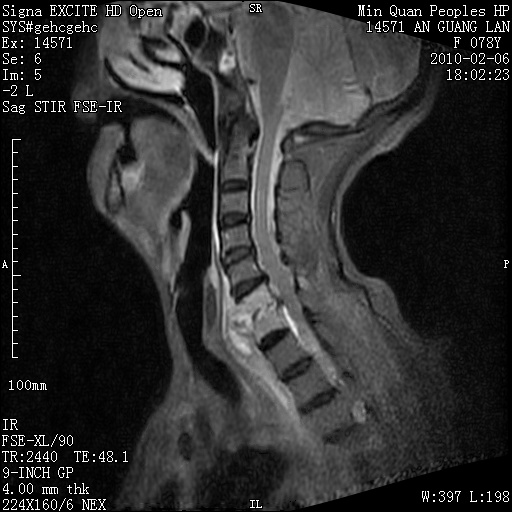

标题: MRI2763:C6、C7椎体病变性质?

f,78y,颈部与双上肢阵发性剧痛40余天。ct可见c6、c7椎体虫蚀样破坏,其间椎间隙变窄(没有图片资料可供上传)。

考虑椎体结核并椎旁脓肿。

支持 c6、7椎体结核并椎旁冷脓肿形成。

考虑:c6/7椎体结核并椎旁脓肿形成,建议增强扫描。